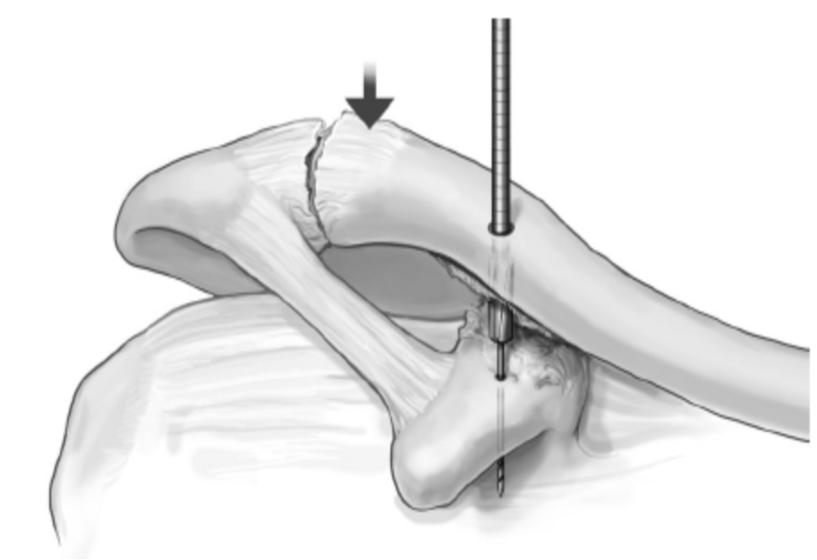

1.复位肩锁关节,1枚克氏针临时固定关节。

2.导针定位,在锁骨远端内侧3cm处自背侧向喙突基底部用4.5mm空心钻头钻孔。

(在锁骨远端钻孔时,钻孔位于锁骨前中1/3处,这样垂直进针才会打入喙突基底正中。)

3.假体准备,在钮扣钢板的外侧和内侧两孔依次穿入2根5号爱惜邦线,袢上穿入1根缝线留作牵引。(测量喙锁间距,选择袢长度要略大于测量值的带袢endobutton钢板。)

4.将钮扣钢板与缝线推至喙突下,将缝线袢向上拉出锁骨表面,在袢下方放入第2块钮扣钢板系紧外侧缝线固定。(注意:放置第二个endobutton时袢的方向要与钢板垂直!还一定要放平以便系缝线!

5.沿锁骨上钻孔的前外侧约1cm处另钻一孔,将内侧缝线打结在该孔上重建斜方韧带。这样就把喙锁韧带重建了。

6.拔出临时克氏针,清洗伤口并缝合。